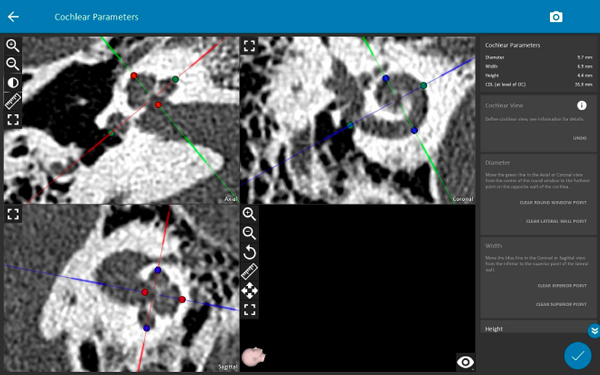

オーダーメイド人工内耳電極選択

高度難聴の原因として、内耳構造奇形があります。その場合、蝸牛全長は変化してきますのでさらに細かい電極選択が必要になります。私たちは2022年OTOPLANシステムによるオーダーメイド人工内耳電極選択を開始しました。手術前に撮影するCTスキャン画像を利用し、内耳の構造(蝸牛長)を計測し(図)、蝸牛全長刺激の概念に基づいて個々の蝸牛の長さに応じて適切な人工内耳電極選択を行います。私たちが主として使用しているメドエル社製人工内耳電極には9種類の長さの異なる電極があるため、その中から選択しています。そして、電極位置から推定される周波数割り当てに基づいた人工内耳マッピングを行っており、より良い聞こえの回復を目指しております。